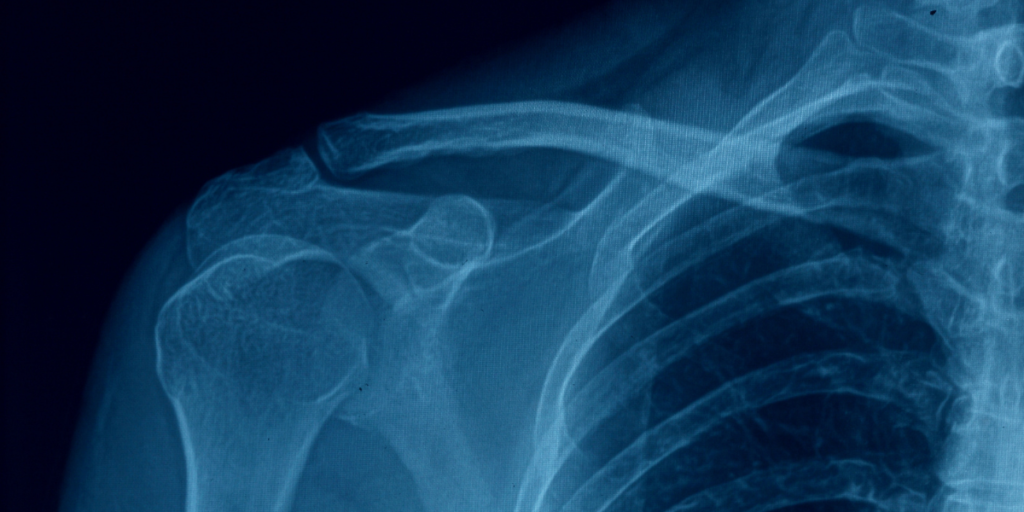

Le immagini ottenute attraverso l’Esame RX Clavicola offrono una visione chiara e dettagliata della struttura dell’osso, permettendo di individuare:

• Fratture recenti o consolidate.

• Lussazioni della clavicola.

• Segni di artrite o osteoartrosi.

• Eventuali anomalie congenite o acquisite.

• Alterazioni della densità ossea dovute a malattie sistemiche o locali.

L’analisi delle immagini radiografiche consente di definire con precisione la causa del dolore o del disagio riportato dal paziente e di pianificare interventi terapeutici mirati.